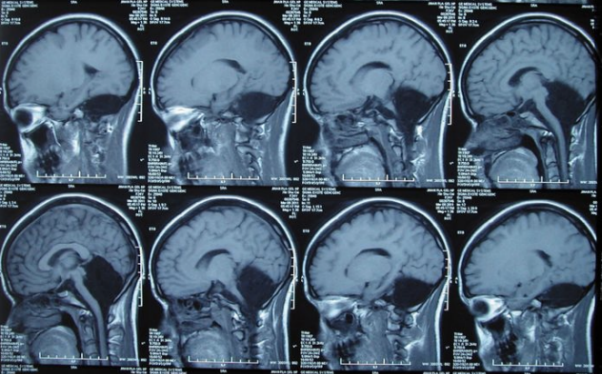

Imaging del cervello di una donna cinese senza cervelletto

Una donna si unisce a un club “d’élite” di nove persone, che viveva senza questa autorità. Descrizioni comunque dettagliate di questo non c’è malattia, poiché tutte le persone sono morte in giovane et� e il problema è stato rilevato solo all’autopsia.

I problemi cerebellari possono portare a gravi disturbi mentali arretratezza, disturbi del movimento, epilessia o potenzialmente accumulo mortale di liquido nel cervello. Tuttavia, a per questa donna, la mancanza di cervelletto ha portato solo a una lieve carenza movimento e moderati problemi di linguaggio, come leggermente sfocato pronuncia.

I medici descrivono questi effetti come “meno di quanto potrebbe essere aspettatevi “e dicono che il suo caso sottolinea l’incredibile plasticità del cervello.